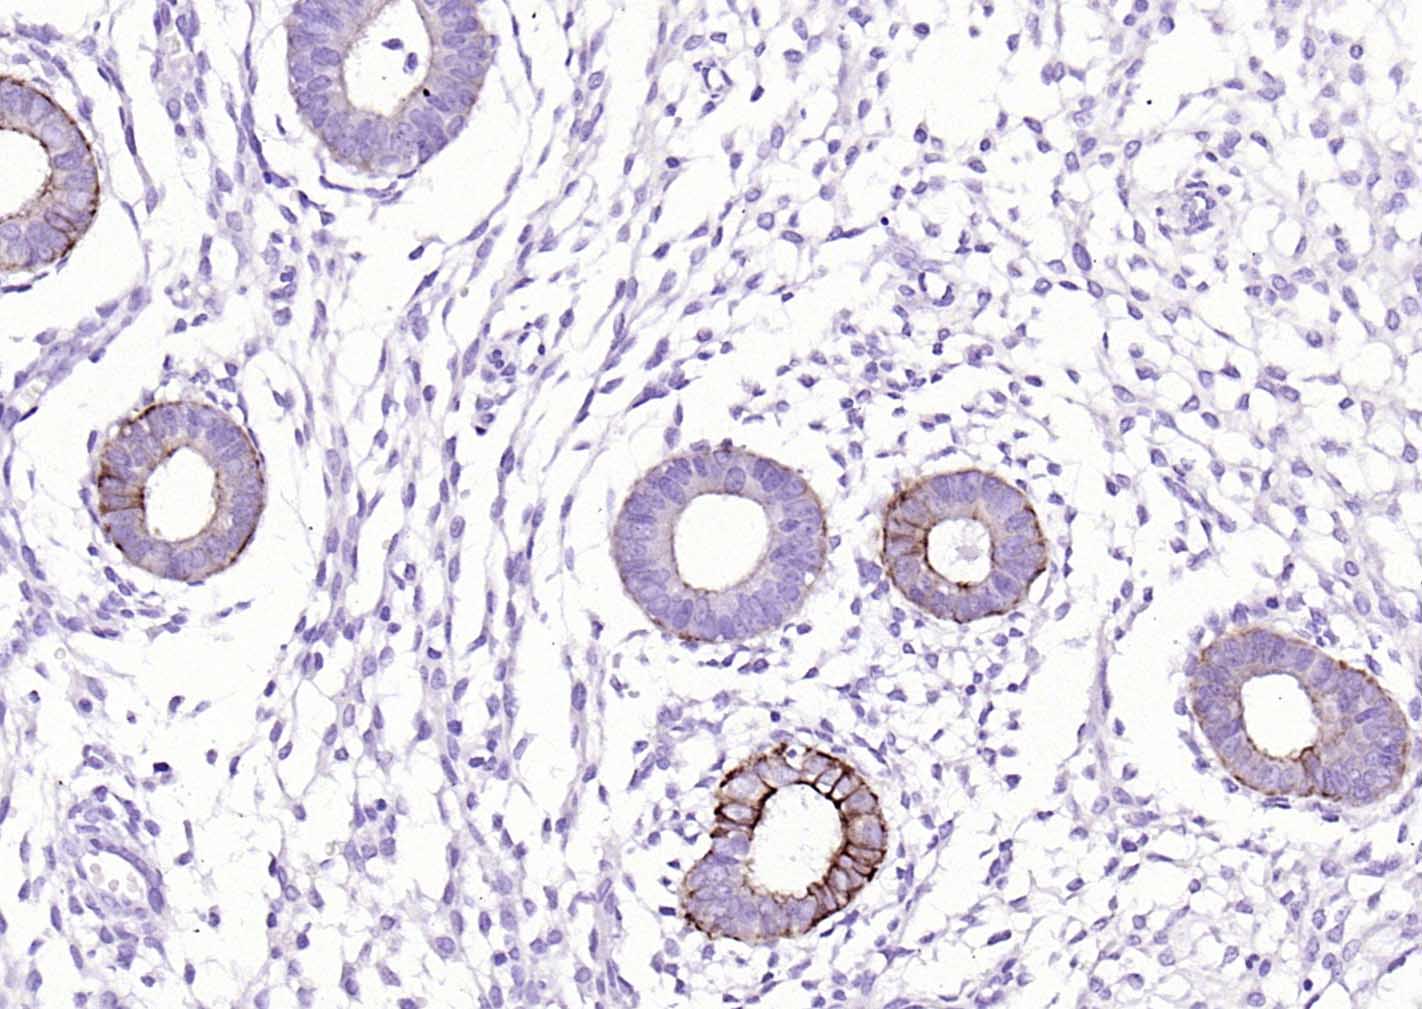

P-CK广谱细胞角蛋白(AE1/AE3)主要标记角化上皮、复层鳞状上皮、复层上皮、增生的角化上皮和单层上皮,用于鳞癌,各种腺癌 、移行上皮癌,小细胞癌,恶性间皮瘤、生殖细胞肿瘤,部分滑膜肉瘤、平滑肌肉瘤等表达。

广谱细胞角蛋白PCK单克隆抗体-bsm-34137M广谱细胞角蛋白PCK单克隆抗体-bsm-34137M广谱细胞角蛋白PCK单克隆抗体-bsm-34137M广谱细胞角蛋白PCK单克隆抗体-bsm-34137M广谱细胞角蛋白PCK单克隆抗体-bsm-34137M广谱细胞角蛋白PCK单克隆抗体-bsm-34137M广谱细胞角蛋白PCK单克隆抗体-bsm-34137M广谱细胞角蛋白PCK单克隆抗体-bsm-34137M广谱细胞角蛋白PCK单克隆抗体-bsm-34137M广谱细胞角蛋白PCK单克隆抗体-bsm-34137M广谱细胞角蛋白PCK单克隆抗体-bsm-34137M广谱细胞角蛋白PCK单克隆抗体-bsm-34137M广谱细胞角蛋白PCK单克隆抗体-bsm-34137M广谱细胞角蛋白PCK单克隆抗体-bsm-34137M广谱细胞角蛋白PCK单克隆抗体-bsm-34137M

IHC-PHuman, Mouse, Rat1:100-500